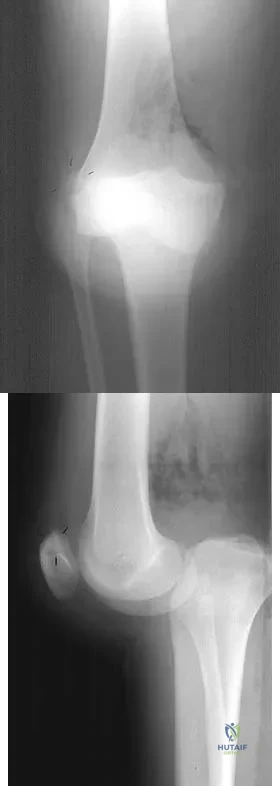

Question 73

Figures 28a and 28b show AP and lateral radiographs of the knee. Based on these findings, which of the following structures has most likely been injured?

Explanation